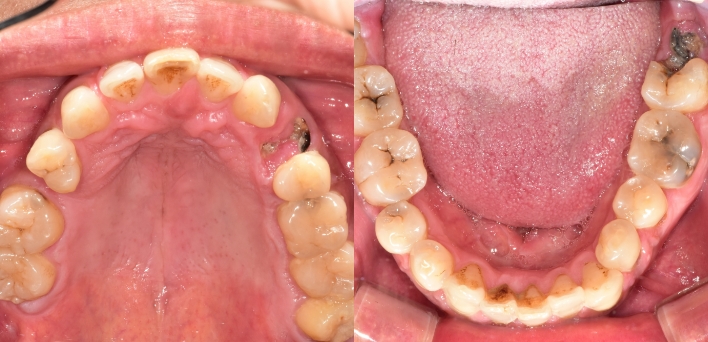

Before Before

2020.02.30

After After

※ 더서울치과의원은 의료법을 준수하며 위 케이스는 실제 환자의 동의를 얻은 사례로 치료 전, 후가 동일한 환경에서 촬영되었습니다.

환자 케이스에 따라 부작용이 발생할 수 있습니다. 이 부분은 의료진의 충분한 상담과 체크를 통해 예방하고 줄일 수 있습니다.

[임플란트 부작용] 수술 후 관리가 소홀할 경우 출혈, 주위염 등의 부작용이 발생할 수 있어 구강 위생을 철저히 유지하고, 정기적인 검진을 통해 상태를 점검하는 것이 중요합니다.

환자 특징

환자 특징01무치악 상태

환자 특징02수년간 무치악으로 지내심

임플란트가 불가능할것이라

생각하고 내원

위, 아래 6개씩 식립

디지털 풀아치 임플란트